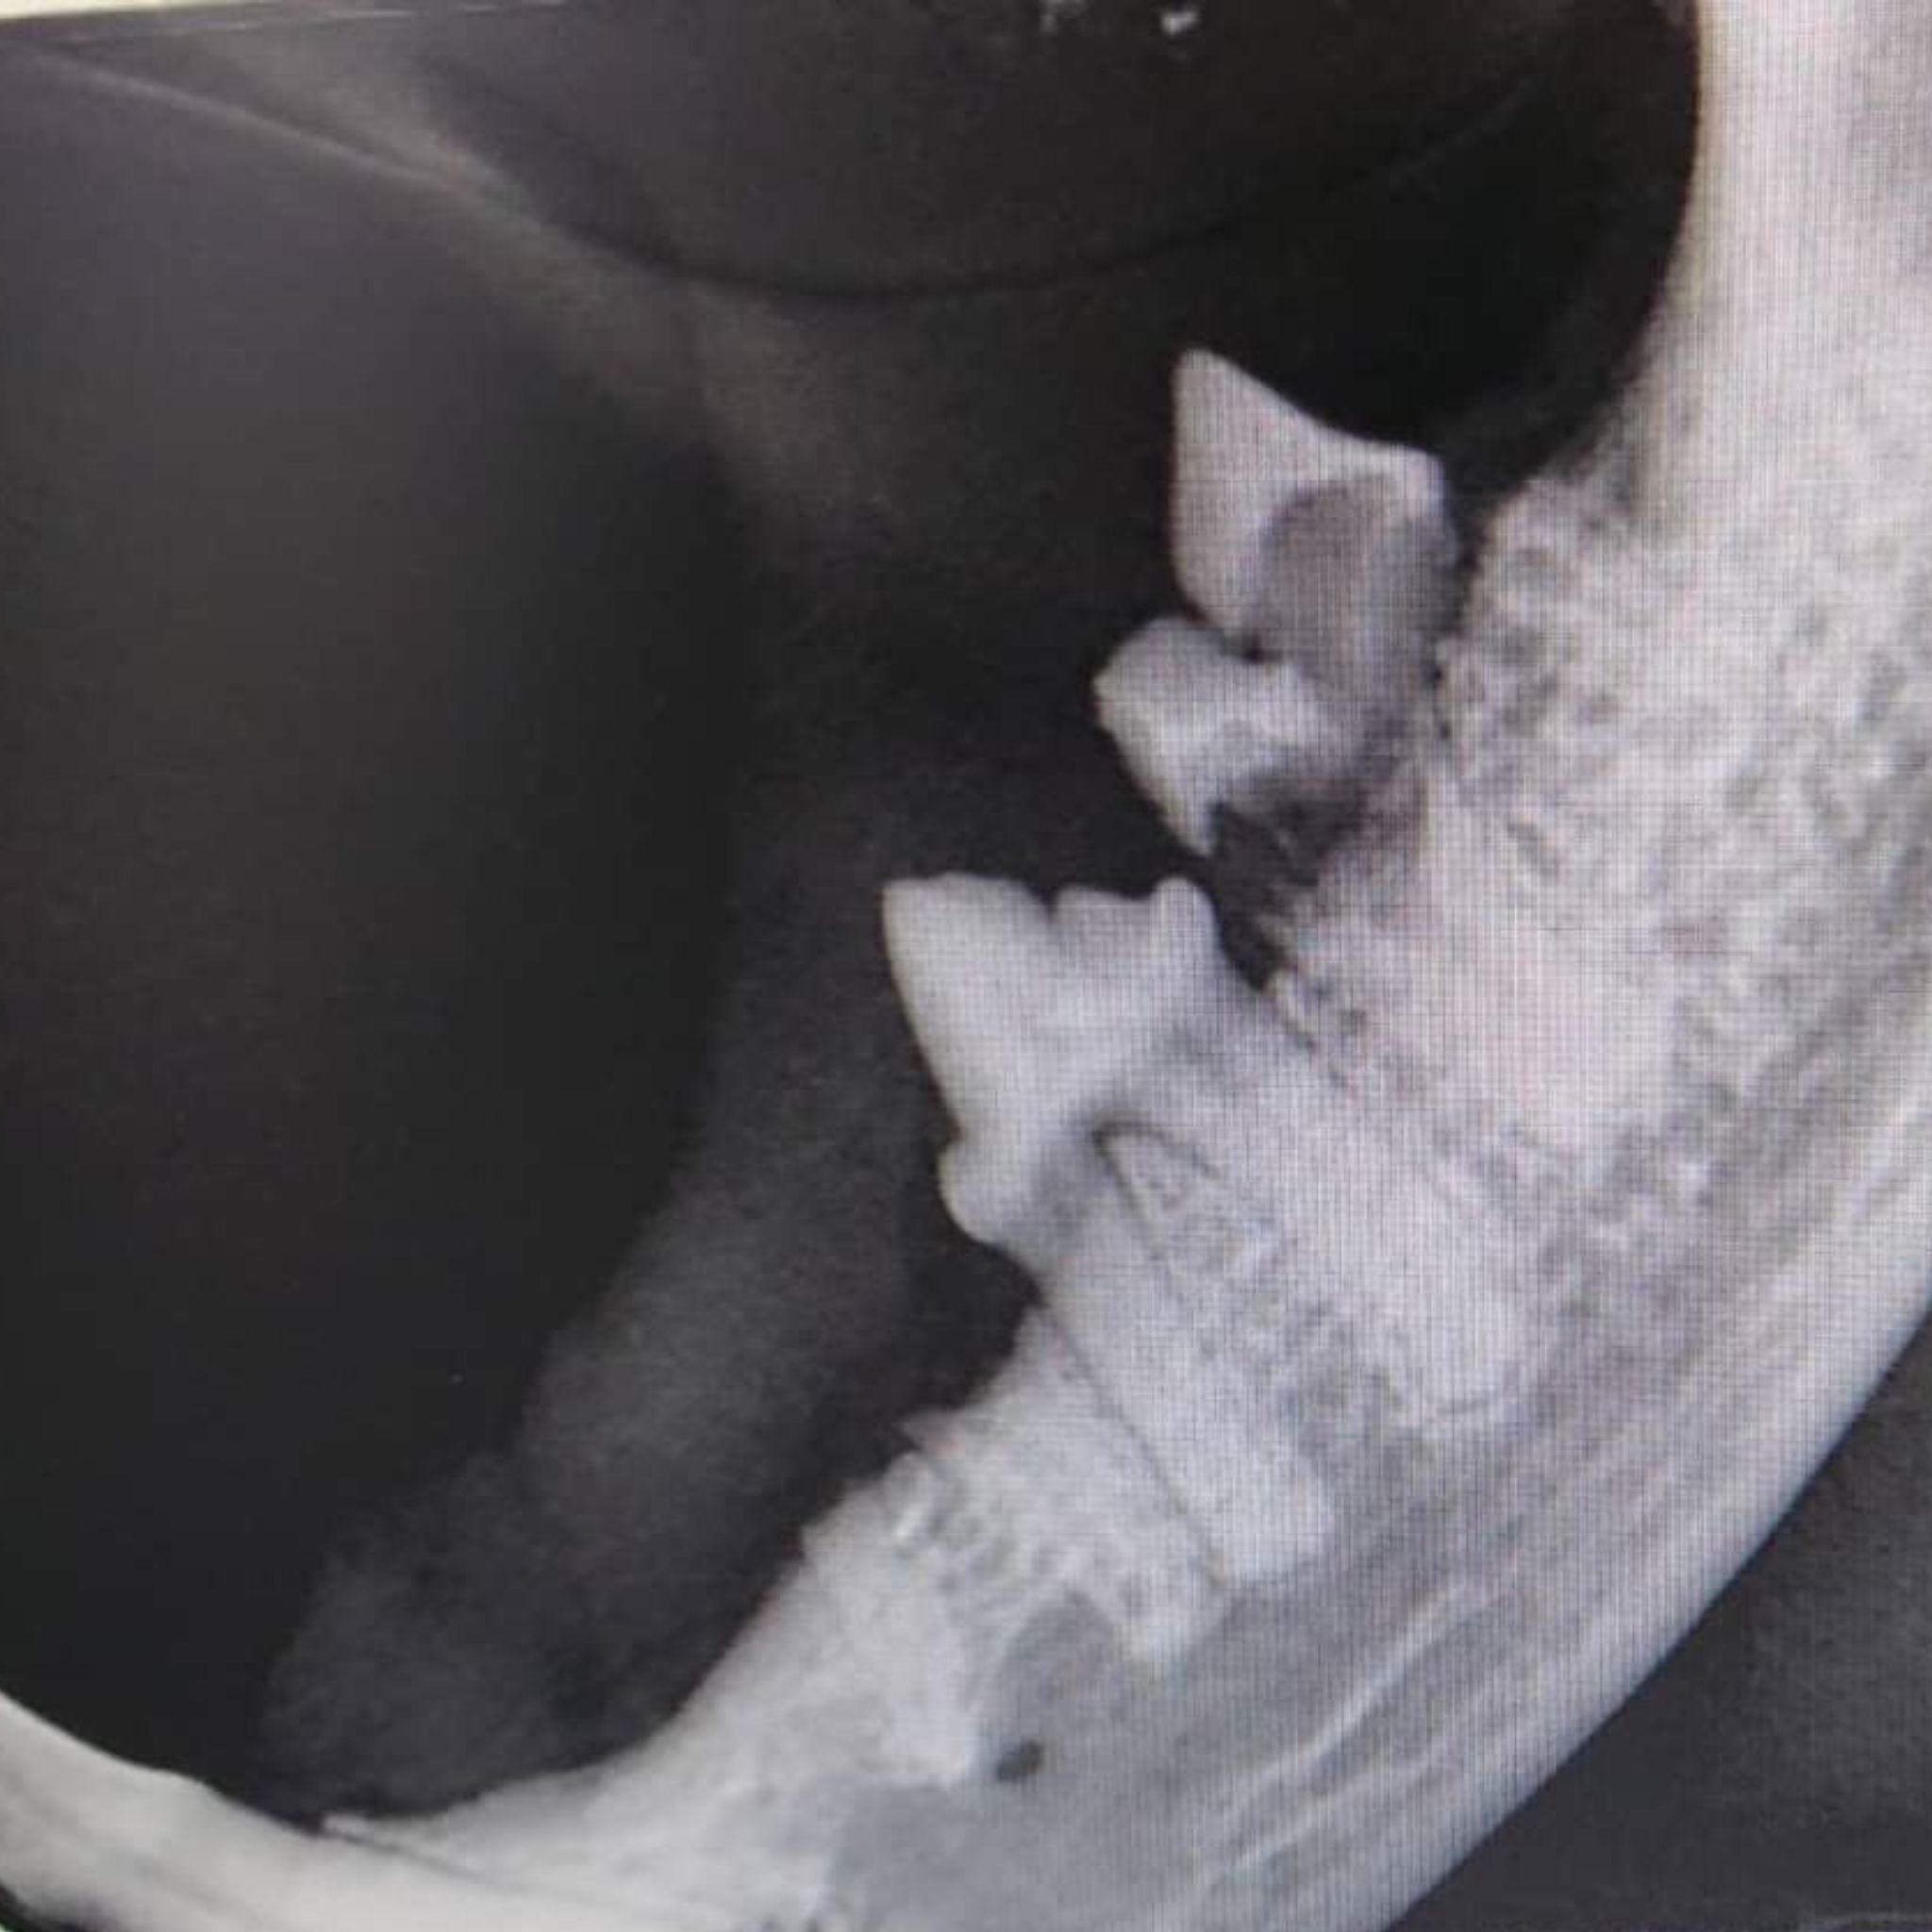

Katzen erkranken besonders häufig an schmerzhaften Veränderungen im Bereich der Maulhöhle. Bereits im Alter von > 3 Jahren erkranken 2 von 3 Katzen laut Studien an Erkrankungen in der Maulhöhle. Die häufigste Erkrankung ist FORL (feline odontoklastische resorptive Läsionen). Die Ursachen für FORL sind bis heute leider nicht sicher geklärt. Wir wissen jedoch, dass es zu einer Aktivierung von körpereigenen Zellen (sogenannte Odontoklasten) kommt. Diese sind eigentlich nur dafür da, die Milchzahnwurzeln bei jungen Tieren abzubauen. Bei ausgewachsenen Tieren sollten sie nicht mehr aktiv sein. Bei Katzen, die unter FORL leiden, werden jedoch die bleibenden Zähne von diesen Zellen „angeknabbert“ und zerstört. Der Abbauprozess des Zahns beginnt meist im Wurzelbereich und wird daher von außen zunächst nicht gesehen. Erst wenn sich der Prozess ausbreitet, kommt es zu äußerlich erkennbaren Veränderungen am Zahn. Diese Zahndefekte sind besonders schmerzhaft und müssen immer behandelt werden. Eine präzise Diagnose und Therapieplanung ist bei dieser Erkrankung nur mit Hilfe von Röntgenaufnahmen möglich, da sich ein erheblicher Teil der Veränderungen im Wurzelbereich abspielt. Auch bei Hunden werden durch Röntgenaufnahmen viele Befunde erhoben, die bei einer normalen Untersuchung verborgen geblieben wären, z.B. Zahnfrakturen durch Spielverletzungen.

Moderne Diagnostik mit Dentalröntgen

Ohne Dentalröntgen sieht man nur die „Spitze des Eisberges“,

denn 65% aller Zahnerkrankungen befinden sich im Zahnwurzelbereich oder Kieferknochen!